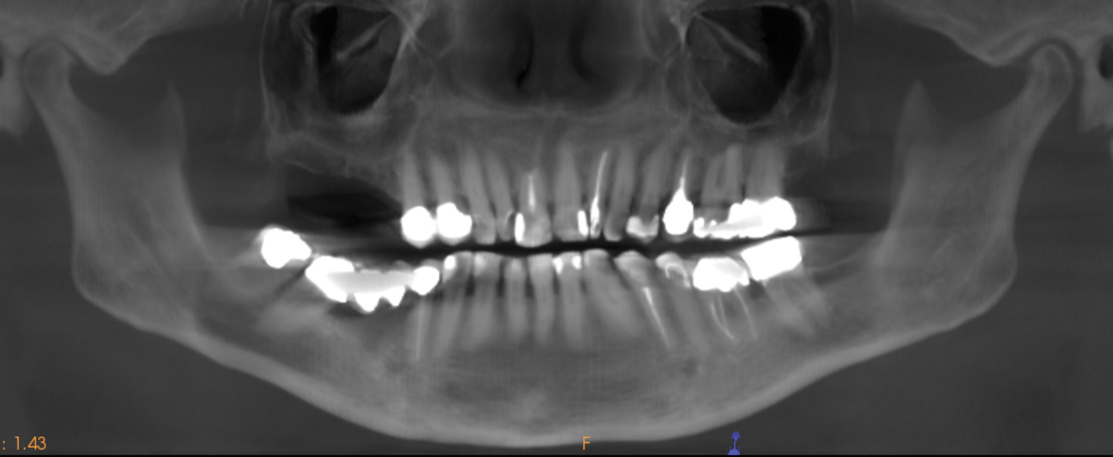

In this first case, OD burs were used at a site requiring maxillary sinus augmentation, an area that is frequently associated with low-density bone. A 60-year-old female patient presented with missing posterior teeth in the right maxillary quadrant. Clinical and cone-beam computed tomography (CBCT) evaluation revealed a partially pneumatized maxillary right sinus with residual bone height of 5 mm (Figure 1 and Figure 2). A lateral sinus augmentation procedure was planned as a result of the minimal residual bone height present and would include simultaneous placement of two implants (one-stage).

Fig 2. CBCT image demonstrating extensive bone loss in right maxillary quadrant with loss of residual bone height in the sinus.

Figure 2